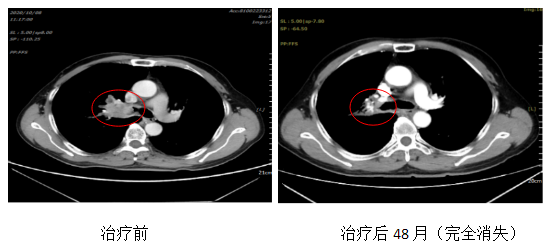

Patient, male, 63 years old, with adenocarcinoma of the right lung, stage: cT2bN2M0 stage IIIA.